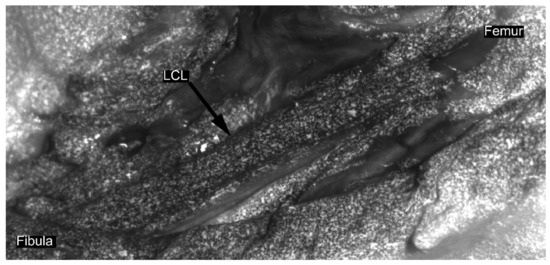

Following ethical approval (NH019 2017-02-03), a pragmatic sample of nine cadaveric knee joints, from five male specimens (age = 83.4 ± 6.69 years; body mass index (BMI) = 27.67 ± 2.77 kg/m2) with total knee implants were collected. Upon clinical inspection by experienced knee surgeons, two specimens showed ruptured LCLs. Consequently, a total of nine MCLs and seven LCLs could be investigated. First, bicortical bone pins were inserted into the tibia and the femur, on which rigid marker frames containing four reflective spheres each were attached, and computed tomography (CT) scans were acquired [15]. One day prior to testing, the legs were taken out of the freezer to thaw. Both the LCL and MCL were exposed, and the joint line was indicated on both ligaments for future referencing.

During the first series of loading cycles, US data were collected with a 38-mm, 10-MHz linear array transducer (Ultrasonix Corp., Richmond, BC, USA). The probe was aligned in parallel with the longitudinal direction of the ligament, centered on the joint line, and a stand-off gel pad was placed between the probe and the ligament. Then, the radiofrequency (RF) and b-mode data were collected dynamically, during loading cycles, at 70 frames per second, with a depth of 2 cm. For each US acquisition, the loading was cyclically repeated until a complete load range was recorded with acceptable image quality, as visually assessed in real time by the experienced ultrasonographer. For each specimen, the acquisition order was randomized between LCL and MCL, and three-to-five acquisitions with visually acceptable quality were obtained per ligament.